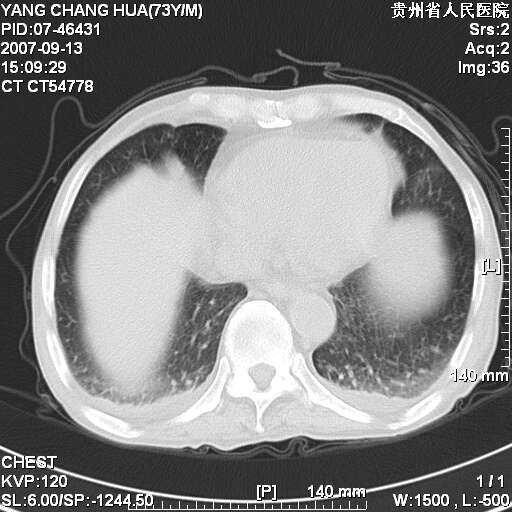

图像没有传全。肺部为感染性病灶;肺囊肿;双侧胸腔积液;肝脾肿大;腹水。

双肺部为感染性病灶.双侧胸腔积液;肝脾肿大;腹水.

双肺部为感染性病灶.双侧胸腔积液;肝脾肿大;脾脏密度不均,不除外脾侵润?腹水.

双肺点片状影,以双上肺改变明显.双侧胸腔积液.为感染性病灶,但不除外结核.

双侧胸腔积液。

双肺散在斑片状及多发小结节状阴影,边缘模糊,双上肺野明显,双侧胸膜腔少量积液,纵隔及肺门区未见明显肿大淋巴结,肝脾肿大,脾内见多发低密度区,结合临床考虑恶性淋巴瘤(肺内表现为肺炎肺泡型),单看影像表现,肺结核不能排除。建议结合实验室检查或表浅淋巴结活检。